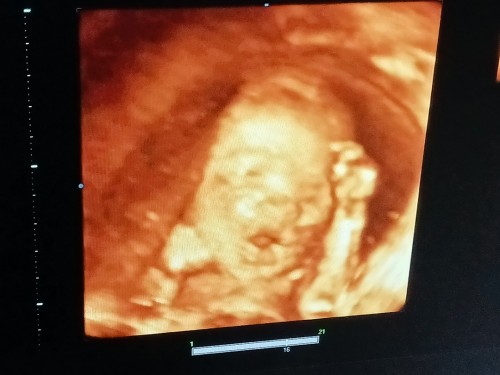

กรกฎาทีมลูกสาว

แม่กรกฎา ได้ลูกสาวหรือลูกชายกันคร้า😍เอามาอวดกันหน่อยคร้า

บ้านนี้ลูกชายครับผม กำหนดคลอด2 กรกฎา

บ้านนี้ลูกสาวค่ะ กำหนดคลอด 17/07/2023 ค่ะ🥰

บ้านนี้หญิง80%ค่ะ กำหนดคลอด 25 กค 66 ค่ะ

บ้านนี้กำหนด 19 กรกฎาคม ได้ลูกชายค่ะ

บ้านนี้ลูกสาวคร่า กำหนด 12 กรกฎา 🥰🥰

บ้านนี้กำหนดคลอด06/07/66 ได้ลูกชายค่ะ

บ้านนี้ได้ลูกสาวคะ กำหนดคลอด 2 ก.ค

บ้านนี้ก็ลูกสาวกำหนดคลอด22/7/66จ้า

ได้ลูกสาวจ้า กำหนดคลอด30 กรกฎาคม

บ้านนี้ลูกชายค่ะกำหนดคลอด15-07-66